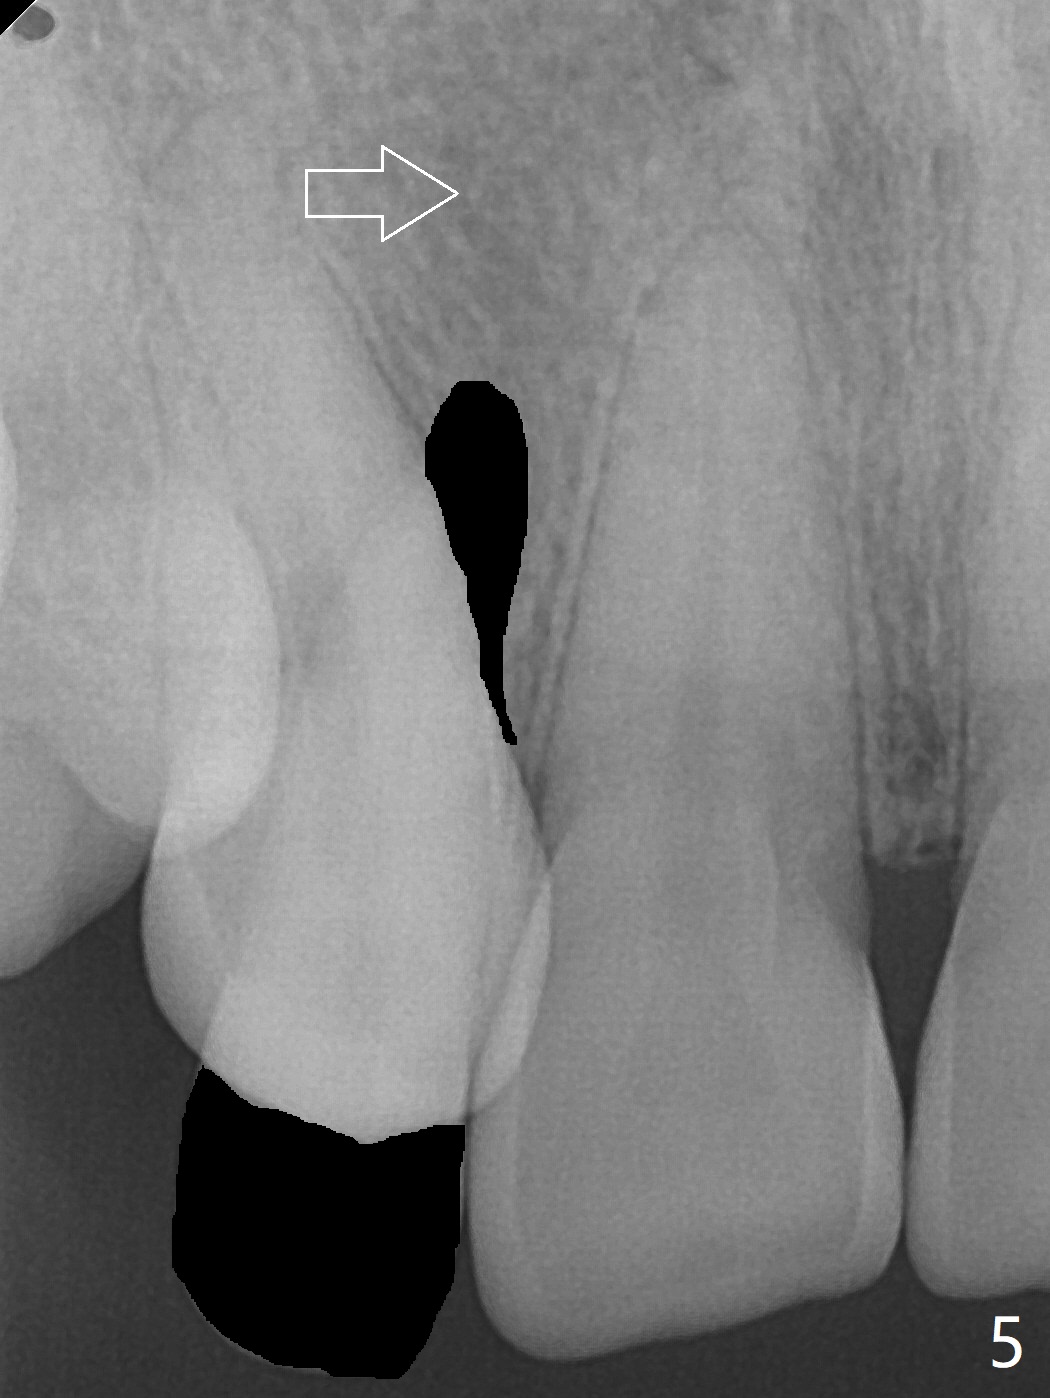

A 54-year-old woman seeks treatment for the tender upper right lateral incisor (Fig.1-4: 2 because of palatal cervical caries (Fig.3 <) and periapical radiolucency (*)), which overlaps with the palatal canine (3). One of treatment options is to extract the lateral and to orthodontically move the canine to the position of the lateral, particularly the root (Fig.5 arrow). When the lateral is removed, the labial bone of the canine is thin (Fig.6). Allograft is placed (Fig.8 * and dashed line), covered with Amnion-Chorion Allograft (Bioxclude) and sutured with 4-0 PGA (Fig.7). The wound heals 9 days postop (Fig.9,10). The patient is grateful because of no pain, which she thinks is due to bone graft, whereas Amnion-Chorion membrane is another contributory factor. The lateral root convexity remains 1 month postop (Fig.11 *); she is undecided upon orthodontic treatment.